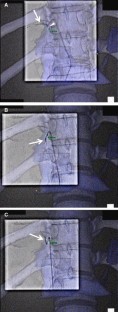

Fig. 1